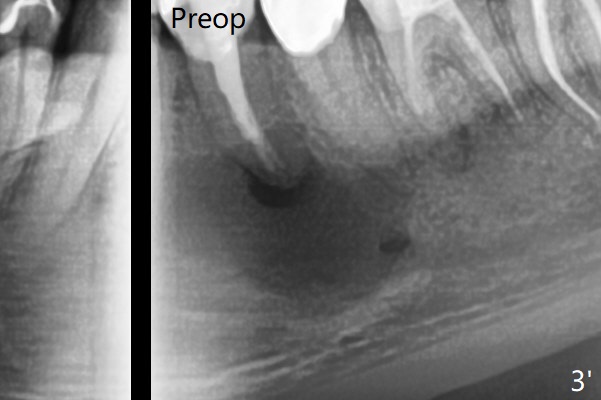

术前冷和电牙髓活力测定显示左下3活髓,不得不做一个长切口和附加切口(图二:>),在暴露颏神经后,在4根尖做囊肿切除术(图一),好像上颌窦外提升,使用上颌窦提升术器械才把囊肿挖出来,不同之处是颊侧骨壁特别厚,为了容易去除4根尖舌侧囊肿,做了根切(图三:<,与图三 ' (术前)对比),但是没做倒充,觉得根管充填完整。并且填入不少粘性骨块(图三)。病理报告:Left Mandibular Body, #21, Excisional Biopsy: Benign fibrous and granulation tissue with acute and chronic inflammation, consistent with periapical granuloma. Negative for odontogenic keratocyst and unicystic ameloblastoma. 左下颌骨体部,21号牙,切除性活检:良性纤维和肉芽组织伴有急性和慢性炎症,与根尖周围肉芽肿一致。牙源性角化囊肿和单房性造釉细胞阴性。术后两个月伤口愈合(图四),骨粉好像安居乐业(图五:*)。